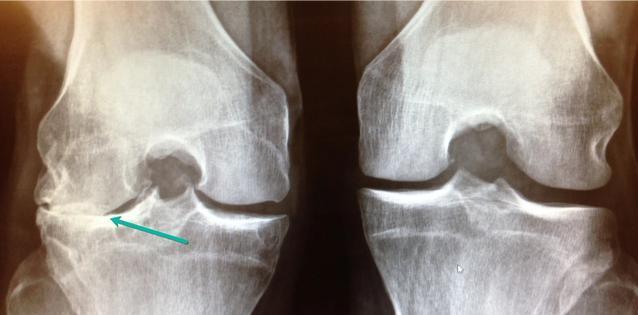

罕见巨大骨软骨块损伤

右股骨内髁软骨全层磨损